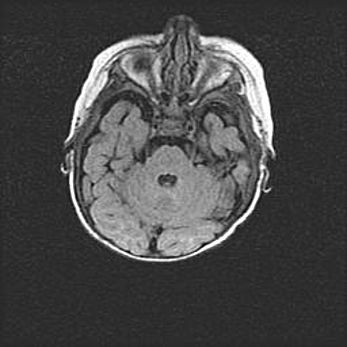

Сообщающаяся гидроцефалия. Кистозная энцефаломаляция головного мозга.

Возраст: 3 месяца 4 дня

Вес: 3100 г

Пол: женский

Окружность головы: 34 см

Срок гестации: 31 неделя

Кистозная энцефаломаляция головного мозга - одна из форм поражения головного мозга в детском возрасте. Характеризуется возникновением множественных и распространённых кист в коре, белом веществе и подкорковых образованиях головного мозга у плодов, новорождённых и детей раннего возраста. Развитие кистозной энцефаломаляции связано с внутриутробной асфиксией и гипотонией, родовой травмой, тромбозом синусов, пороками развития сосудов, инфекциями, сепсисом и другими причинами. Наиболее значимые инфекционные агенты: вирусы простого герпеса, цитомегалии, краснухи, токсоплазмы, энтеробактерии, золотистый стафилококк и другие.